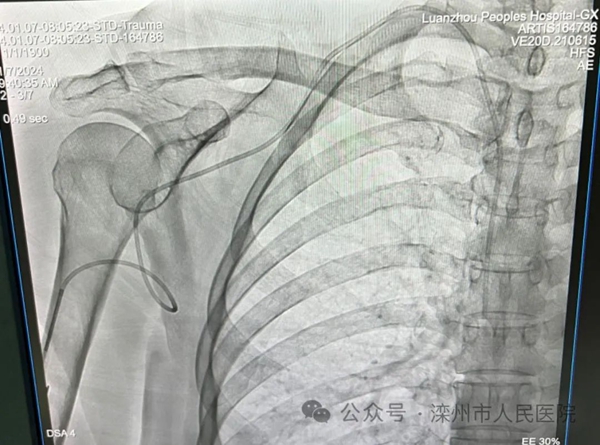

2024年1月7日,滦州市人民医院胃肠乳腺及微创科在复合手术室行超声引导下输液港植入,术中行C型臂拍片调整导管深度,真正做到精准、便捷、一步到位,为化疗病人提供更好的输液选择,给患者带来了健康福音。

植入式静脉输液港又称植入式中央静脉导管系统,简称输液港,是一种可植入皮下、长期留在体内的闭合静脉输液系统,由港座和导管两部分组成,是当前国内最先进的静脉输液技术,能有效解决高压注射问题,可避免因频繁换药或护理维护不当引起感染风险恶和导管脱出或误拔风险等弊端。输液港具有患者舒适度更高,安全性更高,创伤更小、输液港座位置隐秘、维护简单方便等优点,既能极大程度提高患者治疗过程的舒适度和生活质量,又能降低患者日常治疗费用,为广大患者提供了一条更加安全、无痛苦的绿色输液通道。